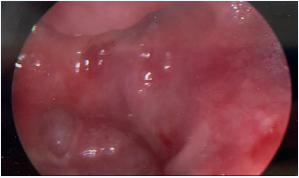

Multiple prior attempts to repair the fistula, including esophageal stent placement, rendezvous procedures (Figure 3),

Figure 3 Fluoroscopic image from a prior unsuccessful rendezvous procedure, indicating the location of the stenosis and the ability to perform the entire surgery through a transcervical approach.

Figure 3: Fluoroscopic image from a prior unsuccessful rendezvous procedure, indicating the location of the stenosis and the ability to perform the entire surgery through a transcervical approach.

and reconstruction with a pectoralis major myofascial flap were unsuccessful. Nearly two years after the initial COVID-19 diagnosis, the patient presented to our institution for consultation. Surgical repair was ultimately performed using a novel technique including tracheal division and esophageal reconstruction with a radial forearm free flap.